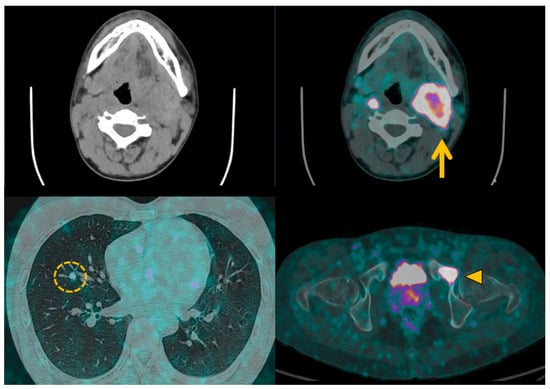

3.5. Head and Neck Parangangliomas: Specific Concerns

4.2. Contributions of Computed Tomography Using Dopamine and Glucose Analogues

4.3. Positron Emission Tomography with Computed Tomography Using Somatostatin Analogues

4.4. Current Guidelines for Molecular Imaging in Diagnosis and Staging of PPGLs